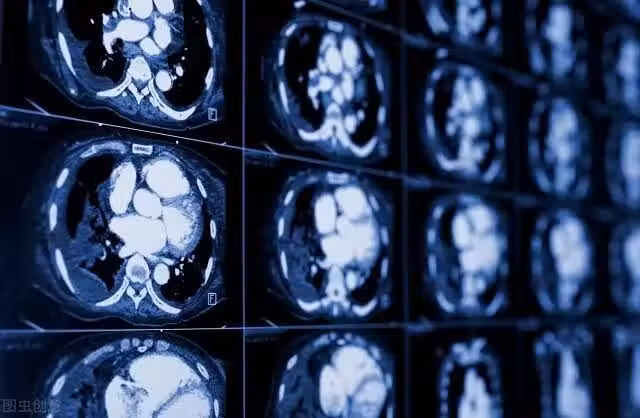

根據美國癌症協會(ACS)的研究,單側眼皮下垂或無力可能源自一種罕見的肺癌,臨床上通常被稱為肺上溝癌或肺尖癌。這種類型的腫瘤位於肺的一側頂部,也就是我們所說的肺的頂端部分,隨著腫瘤的生長,它經常會擴散到神經、胸廓、血管、淋巴結和上椎骨。